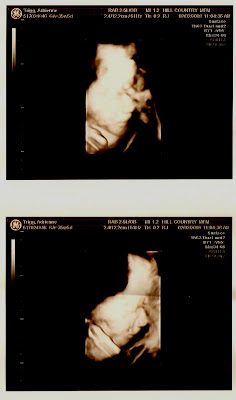

Hayden looked very uncomfortable under my ribs with his feet and hands in front of his face. He is moving well with the little room that he has, but the 3D ultrasound was hard to get this far along with the little amniotic fluid and tight fit in my tummy. The 3D picture is a profile shot with his hand in front of his face and the regular ultrasound picture is a straight on shot of his face.